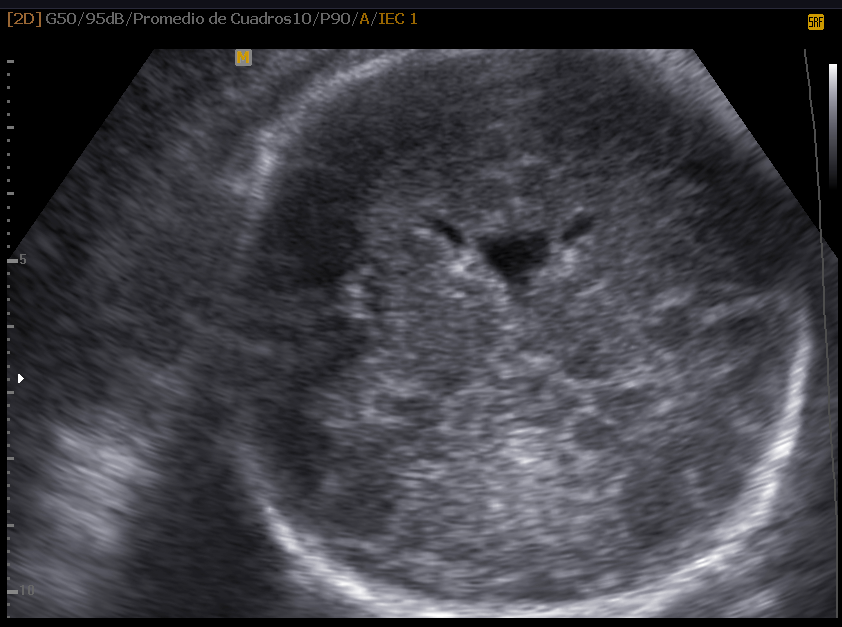

Las estructuras intracraneales después de la semana 18-20 del embarazo son muy características y permanecen visualmente invariables hasta el final del embarazo, solo modificando sus tamaños a medida que el feto crece. Esto es de gran ayuda ya que permite determinar la aparición de cambios que podrían sugerir desviación de la normalidad y aparición de una malformación congénita o lesión adquirida por eventos externos especialmente relacionados a infecciones y accidentes vasculares fetales.

Cuerpo calloso: es una estructura compuesta por haces nerviosos cuya función es la de conectar e integrar regiones corticales homólogas entre ambos hemisferios cerebrales. Su ausencia total puede conducir a problemas cognitivos y del desorrollo psicomotriz o pasar totalmente desapercibida. Su ausencia parcial, paradójicamente, se asocia con peor pronóstico. Como estructura ecográfica, es una de las más bellas que hay en el cerebro pero, para obtenerla se requiere pericia y muy buena resolución ecográfica. Sus alteraciones congénitas son diagnóstico de problemas primarios del desarrollo cerebral y se manifiestan con cambios indirectos en otras secciones cerebrales, especialmente ventriculomegalia.